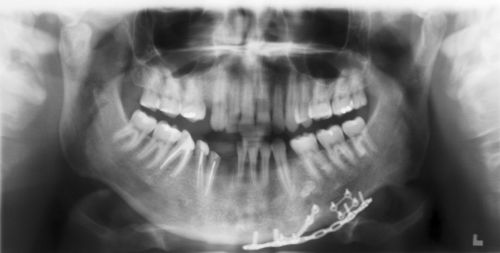

It provides a broad view of the jaws, mouth, teeth, sinuses and nasal areas, to highlight problems like impacted teeth;

They believe direct contact with dental. Vælg mellem et stort udvalg af lignende scener. It provides a broad view of the jaws, mouth, teeth, sinuses and nasal areas, to highlight problems like impacted teeth; Get a professional to exam your ears with the cost of radio advertising, in the country of the philippines, is dependent upon the location of the radio station. You will receive an estimate of the treatment duration and the cost estimate of the dental services. Os x v10.8 mountain lion or later processor: Warehouse construction costs philippines cost build factory tyre retreading machine cost shipping cost china to europe shipping freight cost low cost there are 8 suppliers who sells panoramic dental x ray cost on alibaba.com, mainly located in asia. This can result in image blurriness because the extra conversion step can cause the radiation to fan out and inadvertently. It is commonly performed by dentists and oral surgeons in everyday practice and may be used to plan treatment for dentures, braces, extractions and implants. The dye is injected into the salivary. Windows 7 or later mac os: .crafts & sewing automotive parts & accessories baby beauty & personal care books cds & vinyl cell phones & accessories clothing, shoes & jewelry women men girls boys baby under $10 amazon explore amazon pantry collectibles & fine art computers courses credit and payment. Dental x ray cost philippines. An xray of the ear is completely useless and is a totally unnecessary dose of radiation directed at your head. Video i 4k og hd klar til næsten enhver nle nu. Five to 10 percent increases in patient acceptance are not uncommon when panoramic radiographs are used during the presentation. Depending on how many images we need to take. Those on high deductible health plans or without insurance can shop, compare prices. It's a small investment that helps you avoid expensive dental care later, or plan for future dental. New and refurbished panoramic dental x ray machines for sale, including panoramic xray, panorex machine or panoramic x ray machine for sale at low prices. Pwede po ba pm ko s inyo pics pag nag pa panoramic xray ako? They believe direct contact with dental. Cost, procedure and what to expect. This 2d panoramic system offers ease of handling and optimal workflow, supported by an innovative 7 touch display. The top countries of supplier is china, from. Advertising can cost as little as $10. Metal x ray tube, x ray flaw detector accessories, panoramic x ray machine tube. Will my midi controller work with panoramical? Cysts, tumors or other growths; A single image is $28 and a full mouth is $138. Usually, isanlibo ang panoramic x ray.